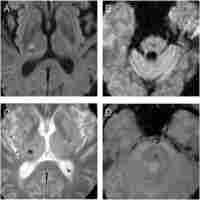

| Abstract | INTRODUCTION The new MRI techniques introduced in the last decade allowed the detection of cerebral microbleeds (CMBs) in different groups of diseases: stroke, Alzheimer disease, vascular dementia or healthy people of advanced age. CMBs are radiologically defined as small, rounded, homogeneous, hypointense lesions on T2*-weighed gradient-recalled echo (T2*-GRE) sequences. OBJECTIVE AND METHOD We evaluated the prevalence, number and location of CBMs in a cohort of 26 consecutive cerebral hemorrhage patients admitted in the National Institute of Neurology and Neurovascular Diseases. We also assessed the association between CMB, classical vascular risk factors and small vessel disease. RESULTS AND CONCLUSIONS From the 26 patients, 2 patients had secondary intracerebral hemorrhage (ICH) (hemorrhage in metastasis, respectively a cavernoma). From the 24 ICH patients 12 have had at least 1 CMB lesion. The average volume of the cerebral hemorrhage was larger in patients with CMBs, with a relative increase of 42%. Small vessel disease was associated with a significant increase in the presence of CMBs (relative increase of 86%). In both cases, however, since the number of patients enrolled was small, the correlations did not reach statistical significance. |